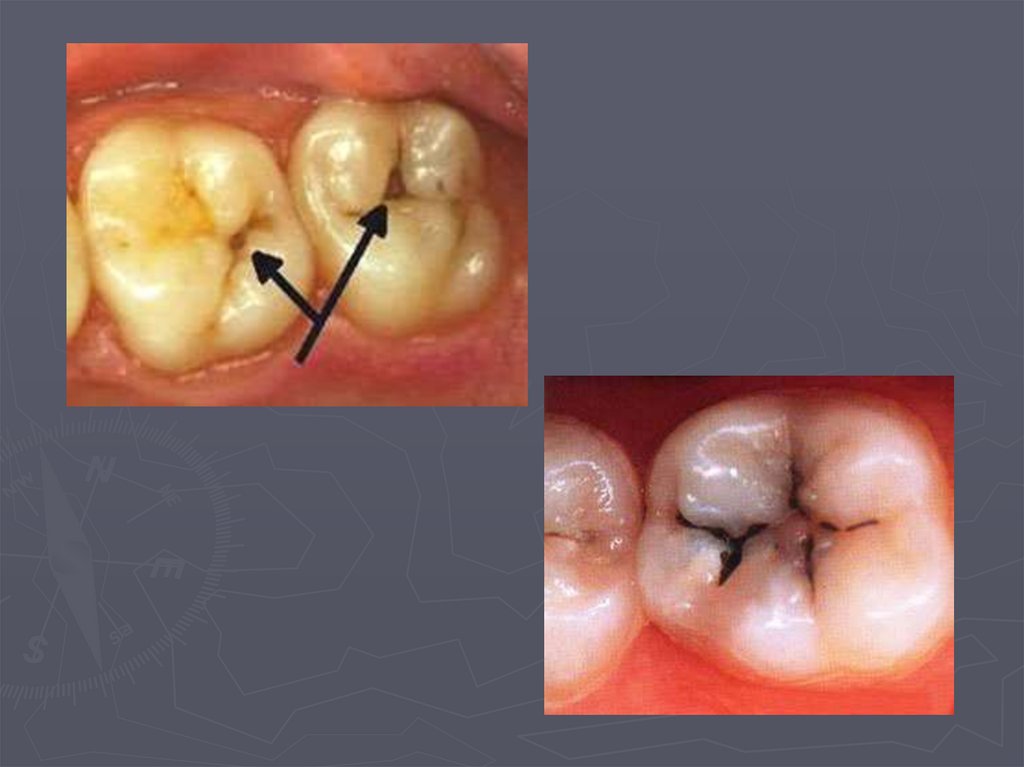

38. КЛИНИЧЕСКАЯ КАРТИНА СРЕДНЕГО КАРИЕСА при декомпенсированной форме:

► при локализации кариозной полости в фиссурах

определяется небольшое входное отверстие;

► при раскрытии обнаруживается кариозная

полость с податливым дентином;

► края кариозной полости нависают;

► эмаль тонкая, хрупкая;

► дентин светлый, влажный, размягченный, легко

удаляется экскаватором;

► зондирование болезненно по

эмалево-дентинному соединению.